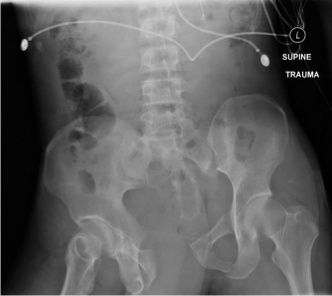

Pelvic fracture

Open book pelvic fracture

Pelvic Fractures

Hemodynamically stable patient (NO PLAIN FILM IMAGE OF PELVIS)

Glasgow coma scale >13

No pelvic, abdominal, or back complaints

No tenderness in the lower abdomen, lower back, groin, or bony pelvis

Hemodynamically unstable patient

FAST

Plain film x-ray of pelvis

Physical examination findings indicating retrograde urethrogram BEFORE FOLEY

Blood at the urethral meatus

High riding prostate

Gross hematuria

Pelvic Assessment